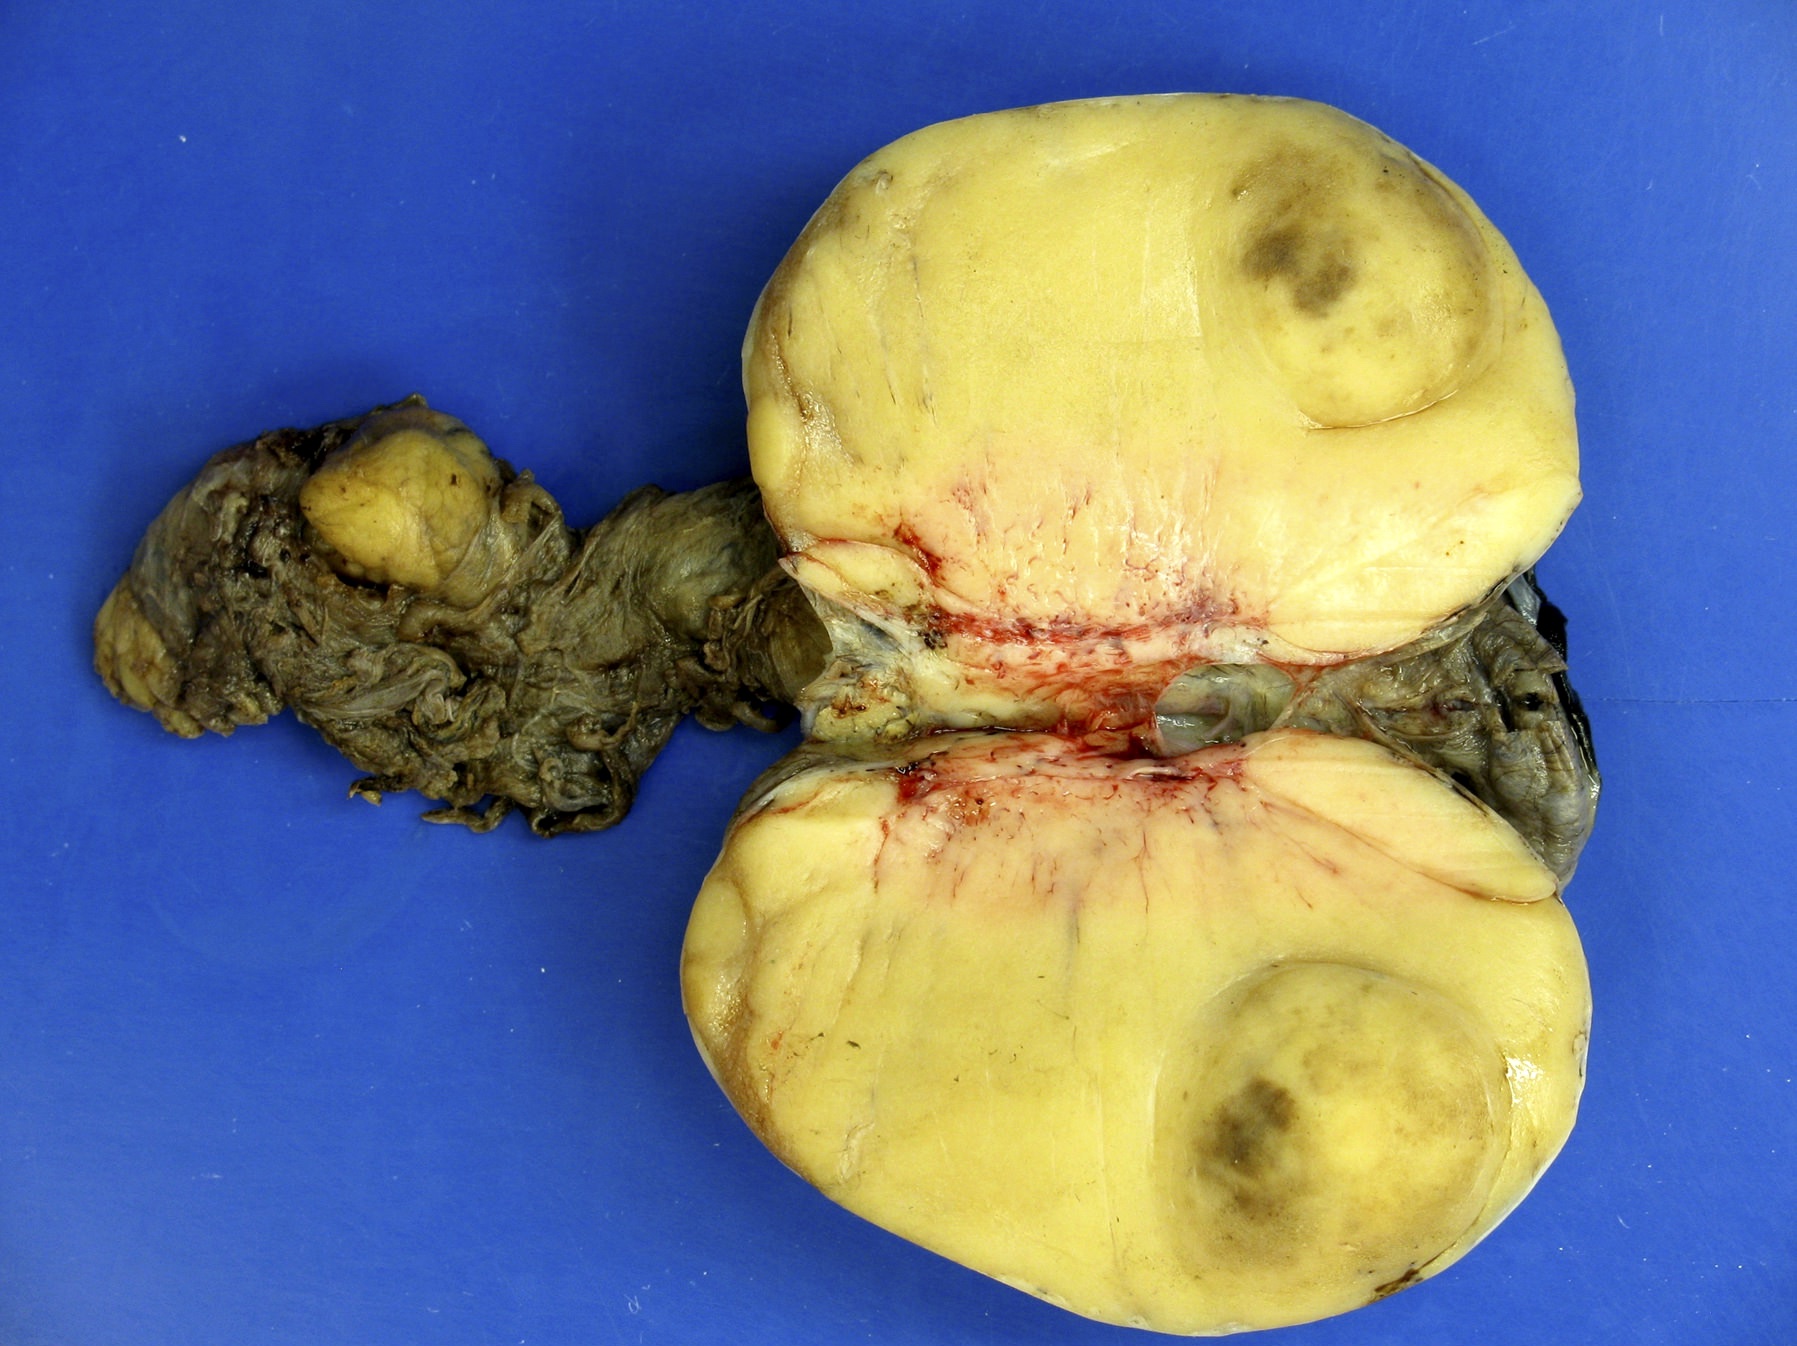

Gross images

Contributed by Debra L. Zynger, M.D.

Mixed germ cell tumor (pT2)

Seminoma (pT2)